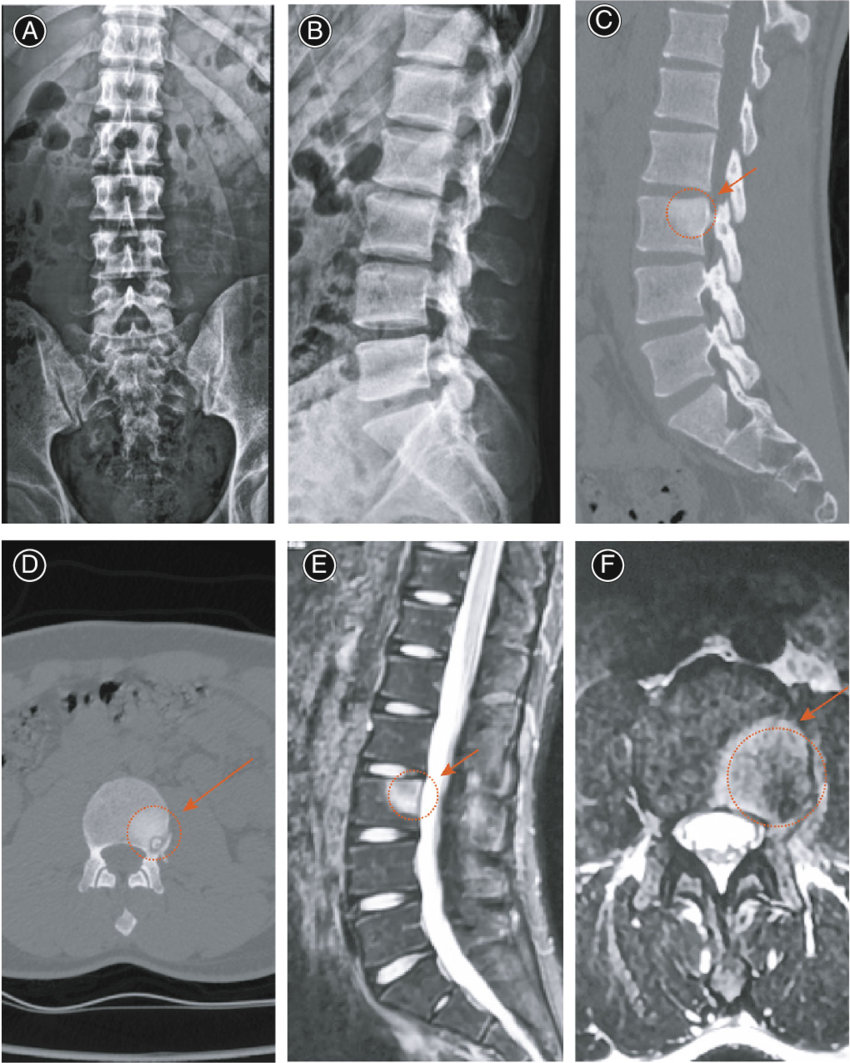

- Kompyuter tomografiyasi (KT): Detallashtirilgan va qatlamma-qatlam tasvir beradi, disklardagi siljishlar yoki artrozni aniqlaydi.